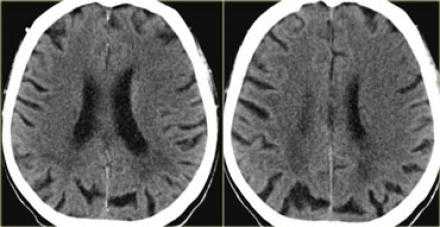

Ранние признаки инсульта на КТ.

КТ является золотым стандартом для выявления геморрагии в первые 24 часа. Геморрагии также выявляются на МРТ. На КТ возможно определить 60% инфарктов в первые 3-6 часов, остальную часть возможно выявить впервые 24 часа. Общая чувствительность КТ при диагностике инфаркта составляет 64% и специфичность 85%. Ниже представлены ранние признаки на КТ.

КТ ранние признаки инсульта.

- — Зона с гиподенсной плотностью головного мозга.

- — Обскурация чечевицеобразных ядер.

- — Симптом плотной СМА.

- — Островковый ленточный симптом.

- — Потеря островковых очертаний.

Гиподенсная зона головного мозга.

Причиной, по которой визуализируется зона ишемии с цитотоксическим отеком, является нарушение работы натрий-калиевого насоса, что в свою очередь связано со снижением количества АТФ. Увеличение содержания воды в мозге на 1% приводит к снижению плотности головного мозга на КТ на 2,5 единицы Хаусфильда. У пациента выше представленного гиподенсивная область головного мозга в правом полушарии. Вытекающий диагноз из данных находок — инфаркт так, как локализация средней мозговой артерии и вовлечение в патологический процесс белого и серого вещества, что типично для инфаркта. Обнаружение в первые 6 часов гиподенсной зоны является специфичным признаком необратимого ишемического повреждения мозга. У пациентов с клиникой инсульта и выявленным гиподенсной областью впервые 6 часов есть риск увеличения зона ишемии, ухудшения симптоматики и кровотечения, а также данная группа пациентов имеет более хуже ответ на проводимую медикаментозную терапию в сравнении с пациентами с клиникой инсульта, у которых данная область не выявлена. Таким образом выявления гиподенсной зоны является неблагоприятным прогнозом. Соответственно, что если гиподенсная зона не выявлена, это благоприятный прогноз.

У данного пациента выявлен гиподенсная область — это инфаркт в области средней мозговой артерии — безвозвратная ишемия головного мозга.